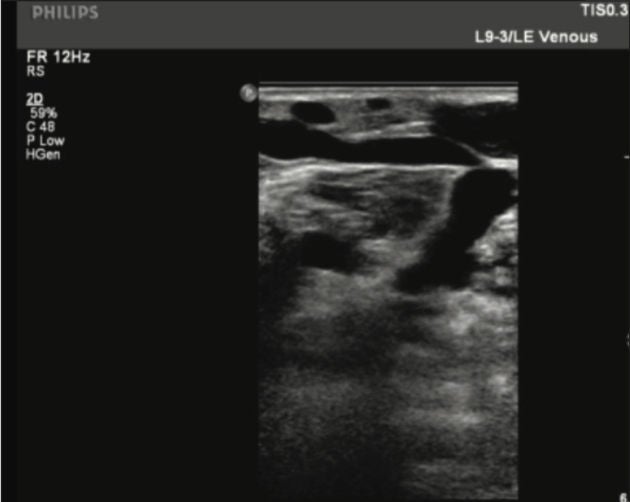

Figure 2. Thigh GSV Tributary one week post- Varithena treatment.

One week post-treatment: Venous duplex ultrasound of the lower extremity revealed a patent deep vein system and occluded GSV throughout the leg. The perforator vein in the calf was patent and compressible. The proximal extent of the thrombus in the GSV was approximately 2.5cm from the Saphenofemoral Junction (SFJ).